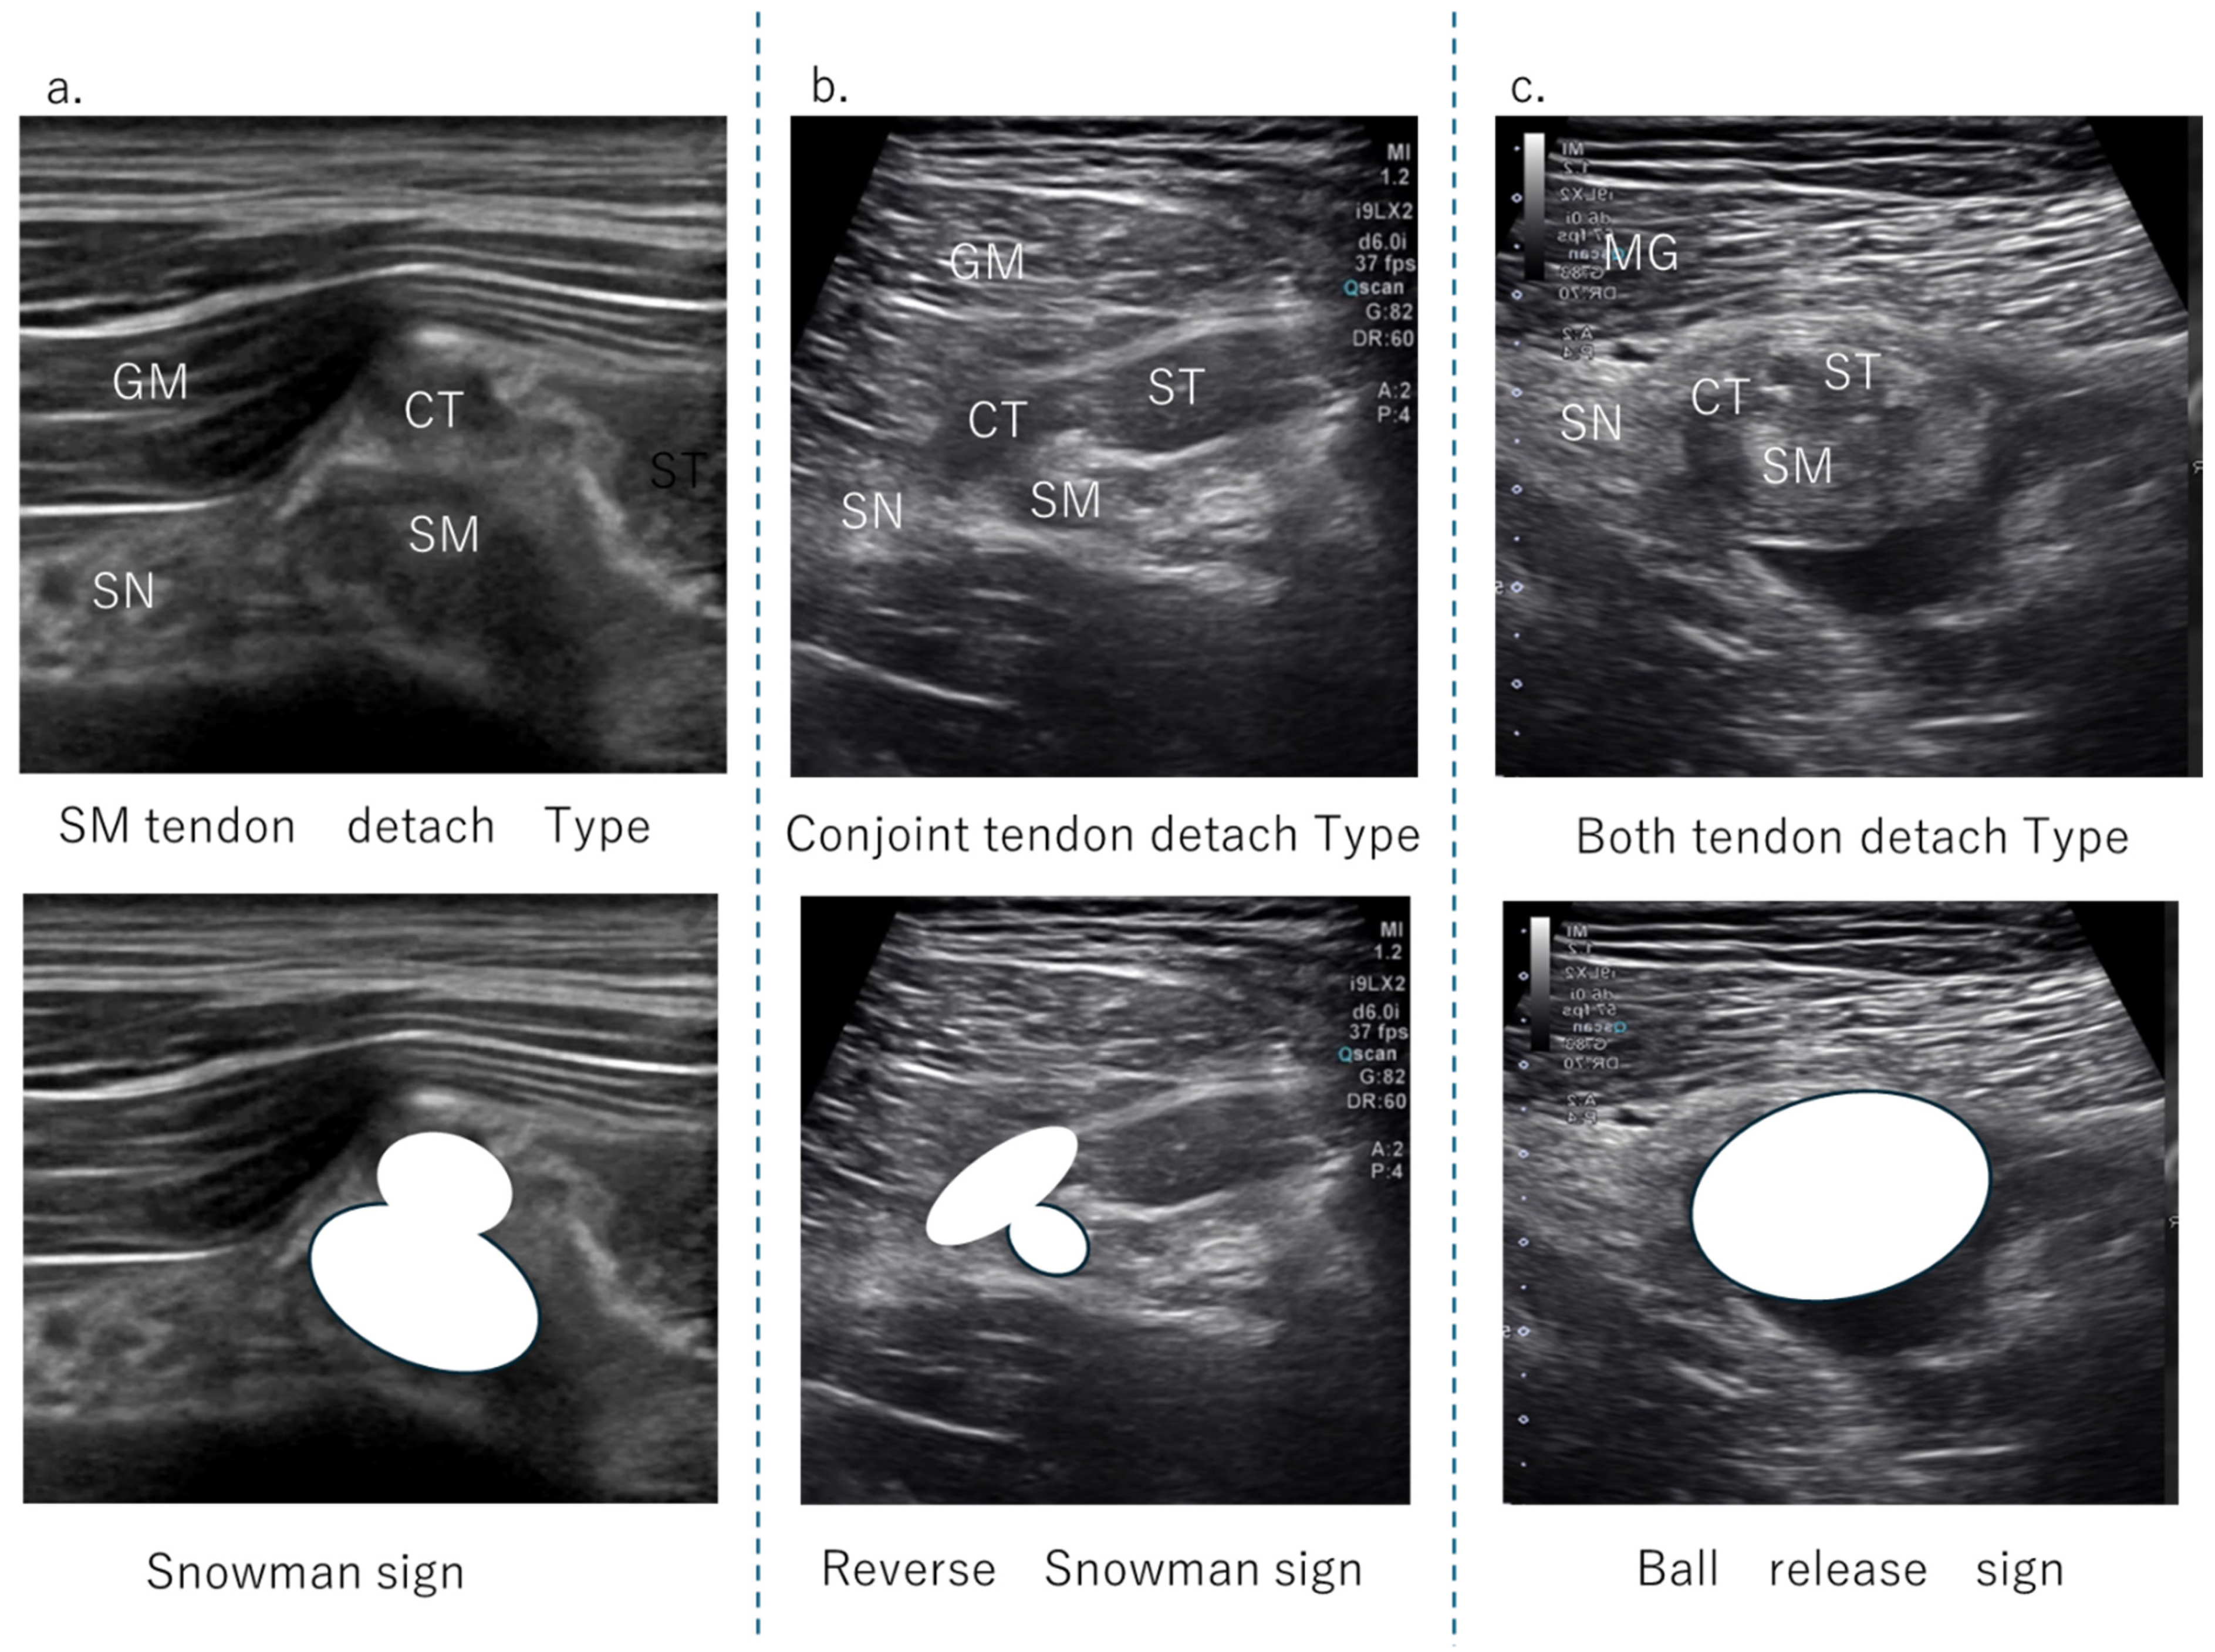

The HMC is a biarticular muscle complex made up of four muscles, three of which originate from the ischial tuberosity with the CT and SMT. The ST is composed of muscle fibers that originate both directly from the ischium and from the conjoint tendon (CT), whereas all BFLH muscle fibers originate from the CT [2,3,8,10] (Figure 2a). Type I injuries are defined as a tear of the CT. As in the diagnostic procedure described above, by carefully observing via ultrasound, it is possible to determine the location of the damage. When performing an ultrasound evaluation of damage to the ischial tuberosity and surrounding area of the origin tendon, such as in CT and SMT, it is easier to see the detached and coiled appearance of the damaged tendon and find swelling if the evaluation is performed at the level where the CT and SMT intersect (Figure 2a, dashed line). The characteristics of the ultrasonic short-axis findings in cases of CT injury and SMT injury and injury to both the CT and SMT are shown in Figure 3. The position of the attachment points of the SMT, CT, and ST muscle fibers are important. The SMT runs through the deep layer of the CT and attaches to the lateral side of the ischial tuberosity. The CT attaches to the medial side of the SMT, and the muscle fibers of the ST attach further to the medial side. The area where the SMT attaches is difficult to visualize using ultrasound in athletes with well-developed gluteal muscles or those with a lot of subcutaneous fat. In such cases, it is useful to evaluate by scanning from the points in Figure 2 and Figure 3 towards the proximal end. The short-axis image of the ischial tuberosity is shown next, in contrast to the MRI image (Figure 4 and Figure 5). In this study, detection by ultrasound was possible for both the BF-ST complex and SM in all but one case, which was a minor injury without conjoint tendon tortuosity or hematoma.

Figure 3. The US findings of the tendon detachment. (a) This is a case of SM detachment from the attachment point. Compared to CT, the SMT that exists in the deeper layers regresses, and the volume in this area often increases, resulting in an image like a ‘snowman sign’. (b) If there is a tear or damage to the CT, the surface layer will become a larger oval, presenting a ‘reverse snowman sign’ appearance. (c) When both the CT and SMT are torn apart as a whole, they are depicted as a single mass, or ‘ball release sign’. This expresses the appearance of the attachment area separating from the ischial tuberosity as a single mass, like a ball.